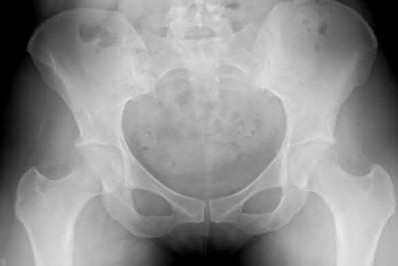

Question 11

A poly-trauma patient presents hemodynamically unstable with an anteroposterior compression (APC-III) pelvic ring injury. A circumferential pelvic binder is requested to reduce pelvic volume and control hemorrhage. To be anatomically effective, the binder must be centered precisely over which of the following landmarks?

Explanation

For optimal mechanical advantage and effective reduction of an 'open book' pelvic fracture (APC type), a pelvic binder must be applied directly over the greater trochanters of the femurs. Applying it higher, such as over the iliac crests, is a common error that fails to adequately close the pelvic ring and can paradoxically open the true pelvis.